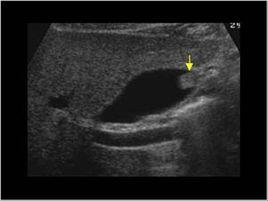

(一)常規超聲檢查:

是診斷膽囊疾病的首選檢查方法,膽固醇性息肉多表現為多發、細蒂、直徑<1cm,但直徑較大的膽固醇性息肉與真性息肉聲像圖相似,鑑別有一定困難。

(二)彩色都卜勒超聲:

是診斷膽囊膽固醇性息肉的首選方法,其能提示發生的部位、數量、形態、大小及蒂的長短、粗細,表面及內部強回聲光團,光團後方有無聲影,隨體位改變息肉有無移動,及膽囊壁改變等。